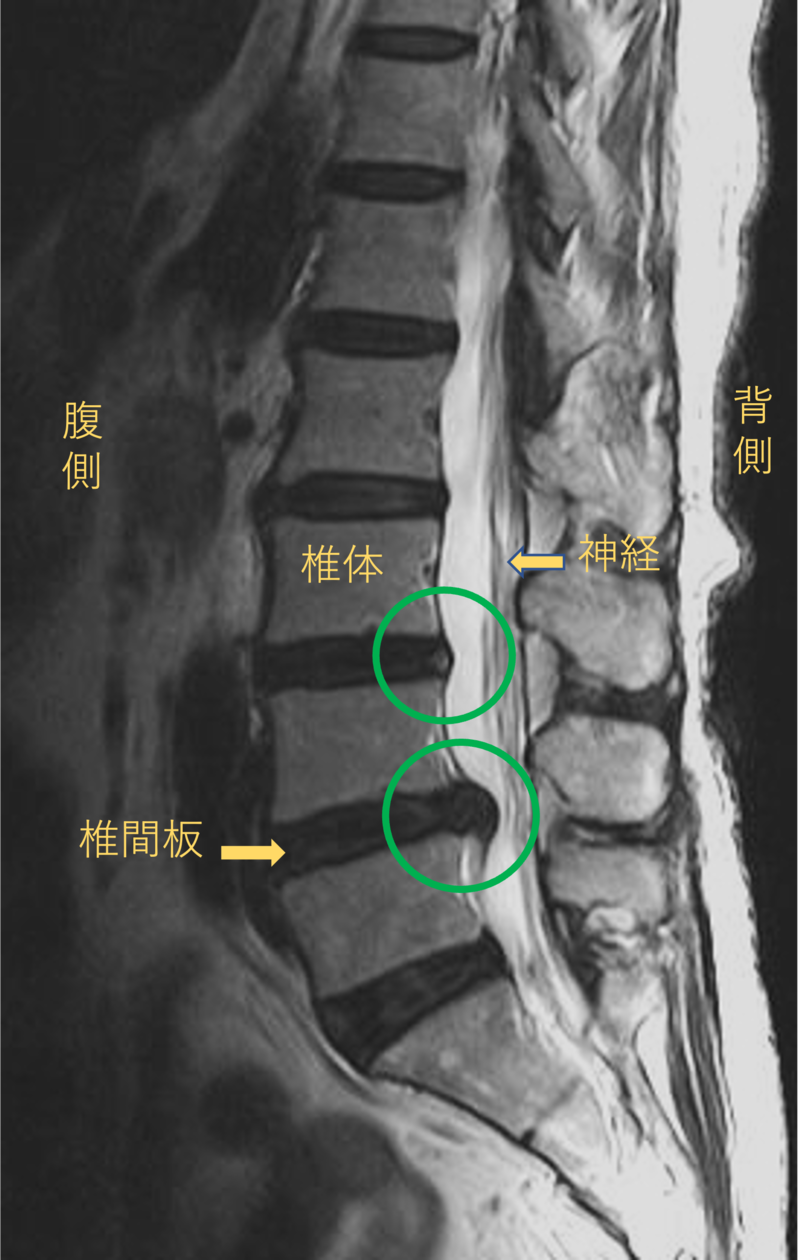

腰を横から見たMRI画像です。

腰椎という骨と骨の間に椎間板と呼ばれるクッションがあります。

このクッションの中身が飛び出す状態が椎間板ヘルニアと呼ばれます。

このMRI画像では、椎間板が背中側に飛び出して足に向かう神経が圧迫されることが痛み、しびれの原因となっておりました。